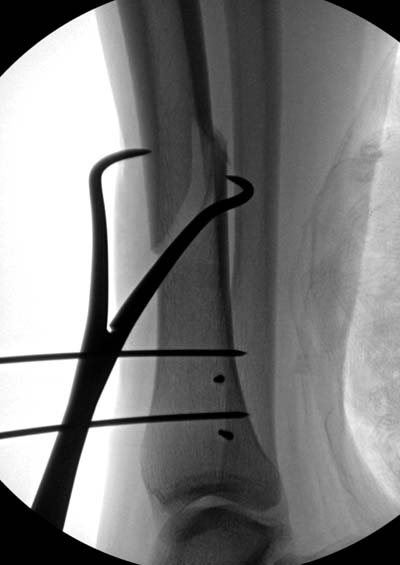

Здесь несколько снимков изолированного перелома большеберцовой с

интактной малоберцовой.  Weber clamp, блокирующие спицы и риминг в

центре канала отрепонировал перелом....